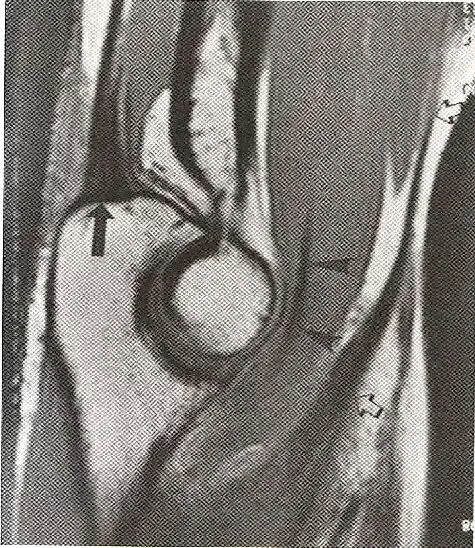

跟腱增厚,纤维束内中等信号,代表粘液样变性和部分撕裂